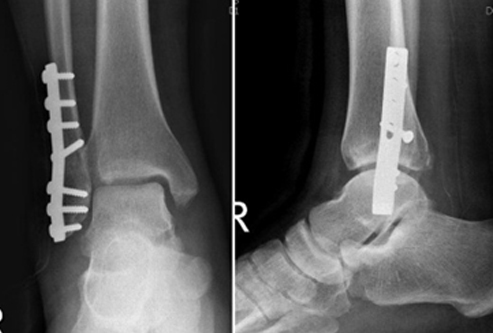

치료의 방침은 크게 도수 정복 후 고정을 통한 비수술적 방법과 관혈적 정복 및 내고정을 통한 수술적 방법으로 크게 나눌 수 있습니다.

그러나, 대부분의 양과 골절이나 삼과 골절은 전위되어 있으며, 이를 마취없이 도수 정복하기는 어렵고, 수술적 가료를 시행하게 됩니다. 골절 후 시간이 지날수록 부종이 심해지고 골다공증이 진행되므로 환자의 상태가 허락한다면, 가능한 수술을 빨리 시행하는 것이 좋습니다. 단, 혈성 수포나 심한 부종이 있는 경우 수술을 연기하는 것이 바람직합니다. 예정된 수술창 부위에 발생한 수포의 경우 터지지 않기까지는 감염성이 없으며, 이에 대한 처치로 저절로 소실될 때까지 기다리거나, 심한 경우 괴사 조직 제거술 후에 치유되고 나서 수술을 시행합니다.